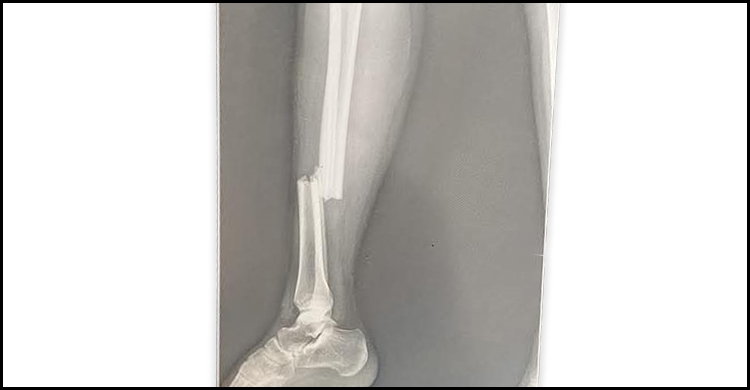

এ বিষয়ে জানতে চাইলে বিশ্ববিদ্যালয়ের প্রক্টর অধ্যাপক মাহবুবর রহমান বলেন, শিক্ষার্থী লিজার ক্যাম্পাস থেকে হলে ফেরার পথে আমাদেরই এক শিক্ষকের ব্যক্তিগত গাড়ির সঙ্গে ধাক্কা লাগে। পরবর্তীতে ওই শিক্ষার্থীকে বিশ্ববিদ্যালয় চিকিৎসা কেন্দ্রে নেওয়া হয়। সেখান থেকে উচ্চতর চিকিৎসার জন্য তাকে রামেকে নেওয়া হয়েছে। এক্সরে রিপোর্ট অনুযায়ী তার পায়ের হাড় ভেঙে গিয়েছে। তাকে রামেকেই ভর্তি করা হয়েছে।